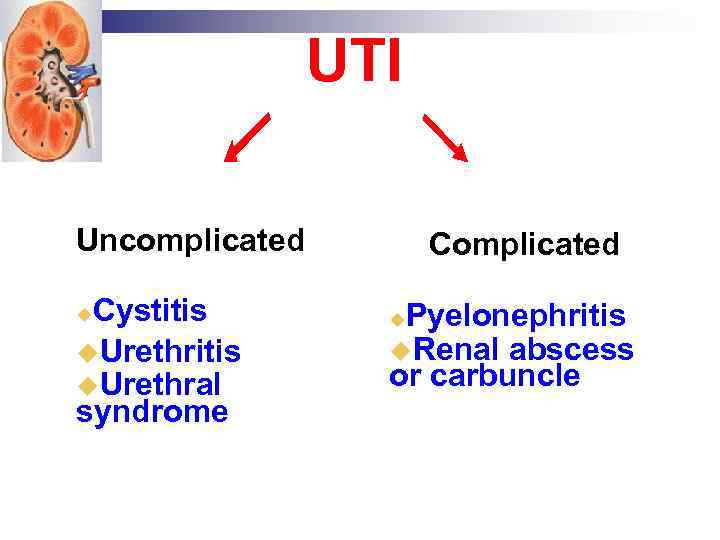

UTI Uncomplicated Cystitis Urethral syndrome Complicated Pyelonephritis Renal abscess or carbuncle

UTI Uncomplicated Cystitis Urethral syndrome Complicated Pyelonephritis Renal abscess or carbuncle